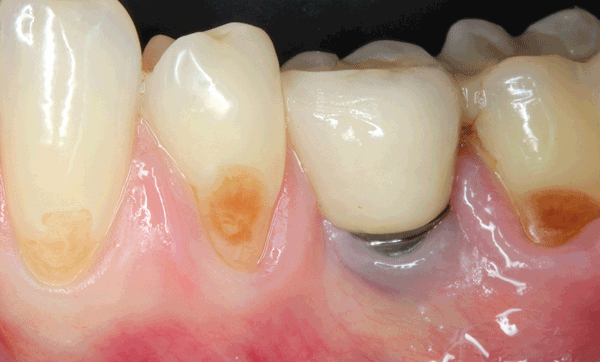

La nécessité de tissu kératinisé autour des dents a fait l’objet d’un long débat en parodontie, et alimente désormais une vive controverse en implantologie. L’importance de sa présence autour des implants reste discutée, et les indications des techniques d’augmentation également. Cette revue narrative a pour but de faire le point sur la littérature dévolue au tissu kératinisé, autour des dents et autour des implants, grâce à dix questions que tout praticien est amené à se poser fréquemment en clinique.

Orban a, pour la première fois, décrit deux parties de la gencive en 1948 : la gencive attachée, fermement adhérente à l’os sous-jacent, et la gencive libre qui la prolonge en direction coronaire, non attachée et délimitant le sillon gingivo-dentaire ou sulcus [1]. Ces deux gencives sont kératinisées et séparées de la muqueuse alvéolaire non kératinisée par la ligne muco-gingivale. La kératinisation est une qualité de l’épithélium qui rend le tissu plus résistant.

Différentes méthodes existent pour repérer cliniquement la ligne muco-gingivale. Le repérage visuel est la plus simple, mais il est parfois difficile. La méthode fonctionnelle consiste à mobiliser la muqueuse, et ainsi repérer la zone immobile correspondant à la ligne muco-gingivale. Cette mobilisation est rendue possible par la présence importante de fibres élastiques dans le chorion de la muqueuse alvéolaire. Enfin, la coloration de Lugol [2] permet de colorer en rouge les glycogènes présents dans la muqueuse alvéolaire et absents dans le tissu kératinisé. Ces méthodes ont été comparées dans un essai clinique, et les auteurs ont conclu à la fiabilité des trois différentes méthodes pour repérer la ligne muco-gingivale, que ce soit avant ou après chirurgie mucogingivale [3].